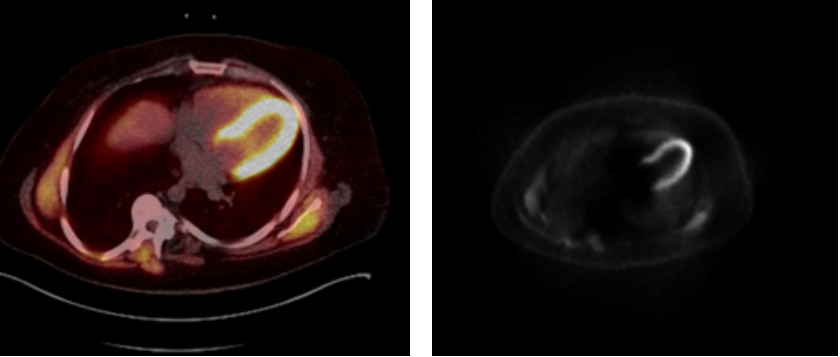

A Positron Emission Tomography (PET–CT (Figure 4) demonstrated no relevant myocardial scar and a Myocardial-Scintigraphy Scan (Figure 5) also failed to demonstrate any evidence of myocardial scarring or ischemia. It was decided in Team Discussion for guideline directed medical therapy (GDMT). Despite of the GDMT, the patient complained of anginal symptoms sometimes even at rest. After 7 weeks of GDMT, the patient presented again to the emergency with recurrent angina (3-4 days) for more than 30 minutes and Angina pectoris (CCS) Canadian Cardiovascular Society grading (class III). The Laboratory investigations revealed raised cardiac enzymes. The transthoracic echocardiogram revealed reduction in the left ventricular ejection function (LVEF of 42%) with mild inferior wall hypokinesia. The case was again re-evaluated in Heart Team Discussion and the option of an operative Revascularisation was given.

Figure 4 PET-CT.

Figure 5 Myocard Szintigraphy.